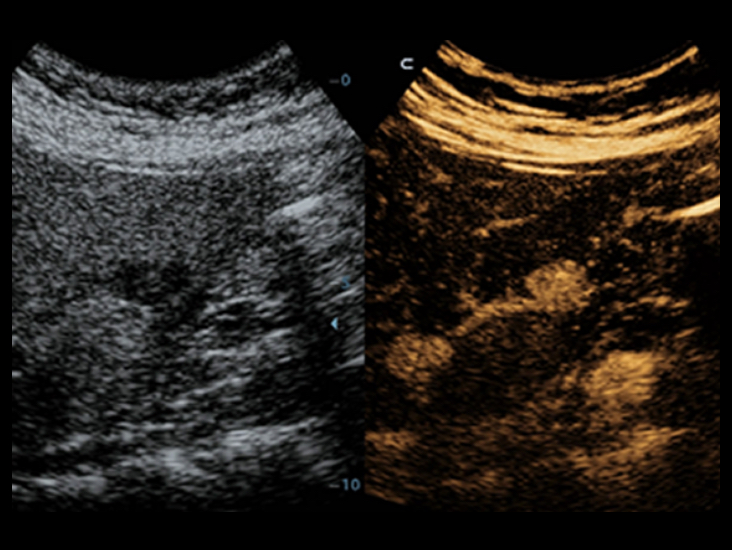

Seri produk transduser yang dioptimalkan: cakupan aplikasi yang luas

Dengan kombinasi transduser serbaguna, DC-40 dengan Full HD menghadirkan keseimbangan kinerja terbaik dalam berbagai jenis aplikasi, dan menghasilkan mutu gambar yang lebih baik untuk berbagai macam jenis pasien.